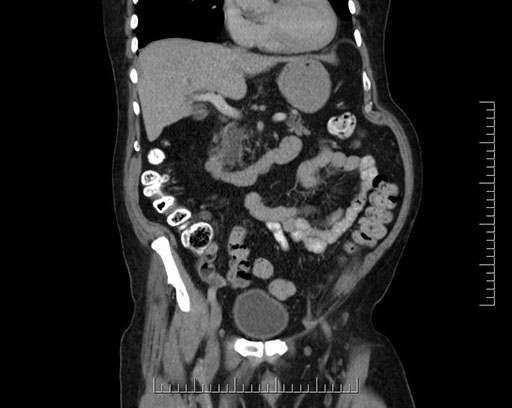

Whipple (pancreaticoduodenectomy) [case 7]

Imaging Analysis

Look through the patient's CT scan to identify any areas of concern for the necessary procedure.

Coronal - stented